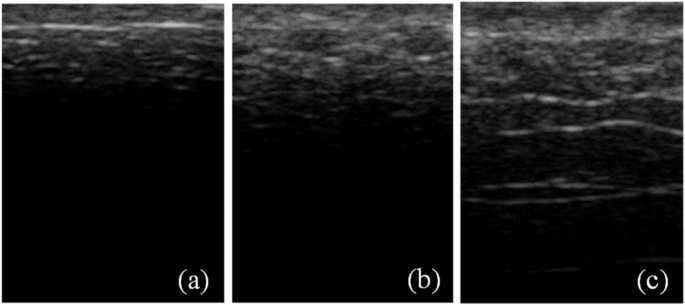

The ultrasound images of ex vivo porcine skin tissue (Figs. 5 and 6) show increased speckles with increasing burn severity. The speckles consist of low-intensity pixels in the ultrasound images. From Fig. 5, we observe that the speckles not only gradually appear along the depth of the skin but also grow with increasing burn severity starting from the unburned (Fig. 5(a)) to the most severe burn at 200 °F for 30 s (Fig. 5(c)). Similar to Figs. 5 and 6 shows the growth of speckles with increasing burn severity from the unburned (Fig. 6(a)) to the most severe burn at 450 °F for 30 s (Fig. 6(c)). The speckles are a manifestation of microstructural degradation of soft hydrated tissues subjected to the applied heating. The water trapped in intra- and extra-cellular spaces evaporate by absorbing the applied heat, resulting in a large acoustic impedance difference between the vapor filled pores and the surrounding tissue52. Similar acoustic impedance difference can also be expected due to the altered structural integrity of the burned tissue as shown in the histology images in Fig. 7. Thermal treatment of tissues is known to change the acoustic impedance of tissue53. The speckles in the ultrasound images appear due to the interference of strong scattering signals from the regions of contrast acoustic impedance acting as “ultrasound contrast agents” (UCAs); thereby greatly improving the contrast-to-tissue ratio (CTR) of the ultrasound images. As we saw in the results section, this greatly enhances the accuracy, sensitivity, and specificity with which burn severity can be classified. The presence of large acoustic impedance difference between UCAs and surrounding tissue is known to greatly improve the CTR in the clinical ultrasound images52.